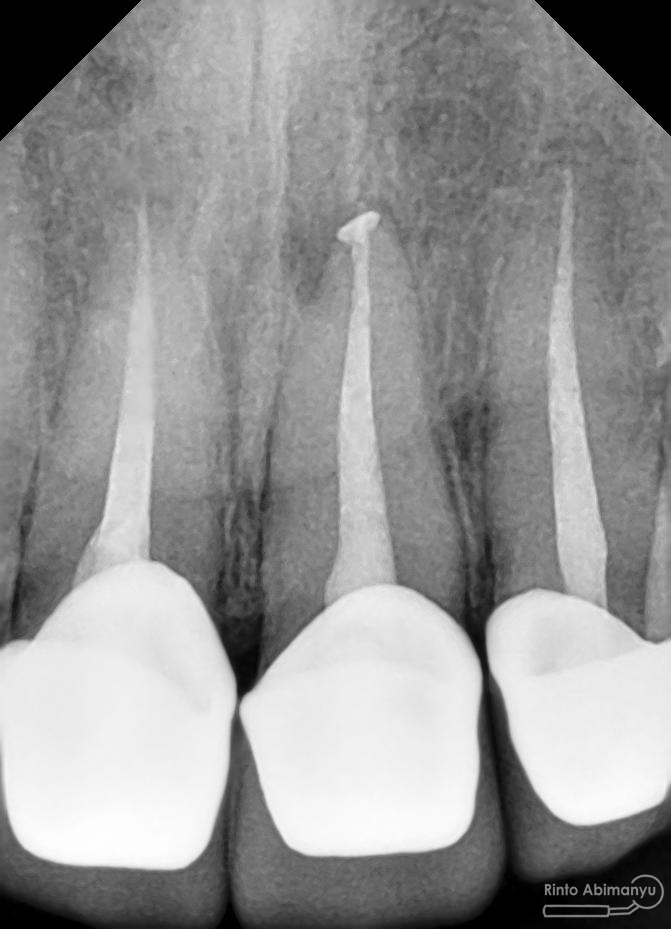

Oo iya tidak lupa juga dilakukan foto ronsen setelah pemasangan crown…

Foto radiografis akhir

Dari foto ronsen terlihat gambaran yang “indah” dari mulai pengisian saluran akar yang rapat dan padat serta gambaran sementasi mahkota yang terlihat homogen….